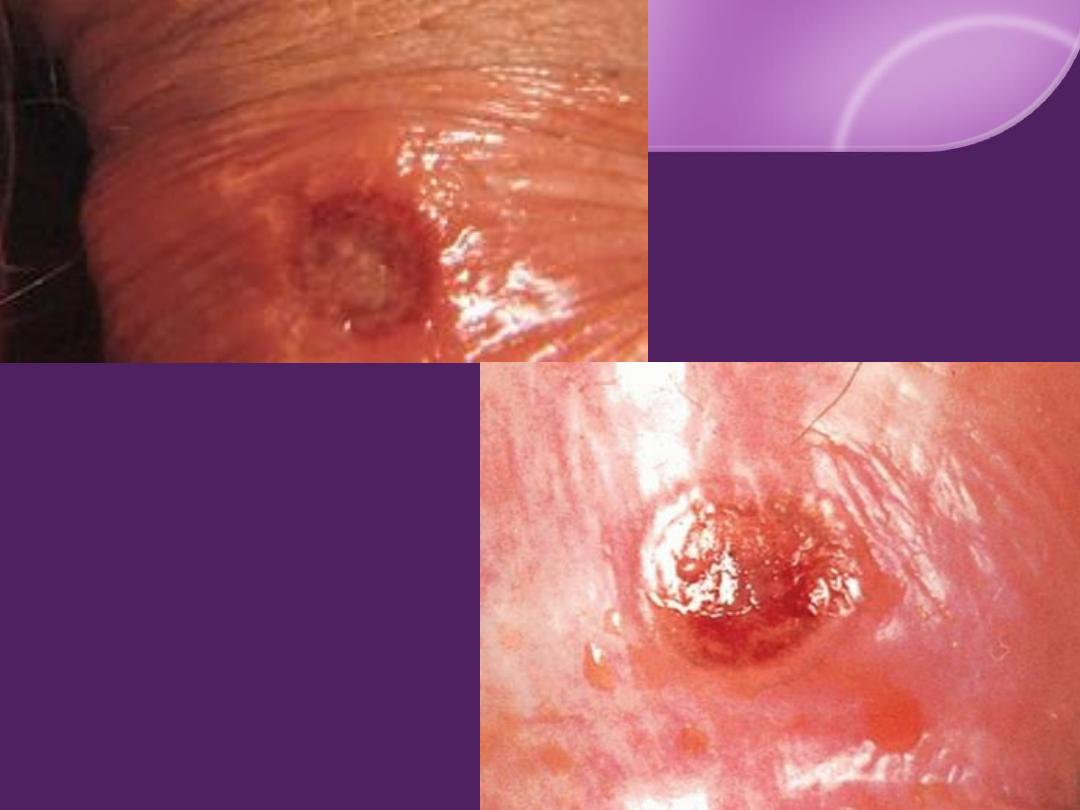

Primary Syphilis (chancre) :

The syphilitic ulcer (

chancre

)

IP: 9-90 days (3 weeks in

50%

)

Solitary

,

painless

,

hard

,

clean base (

50%

)

Painless, hard, discrete regional LN.